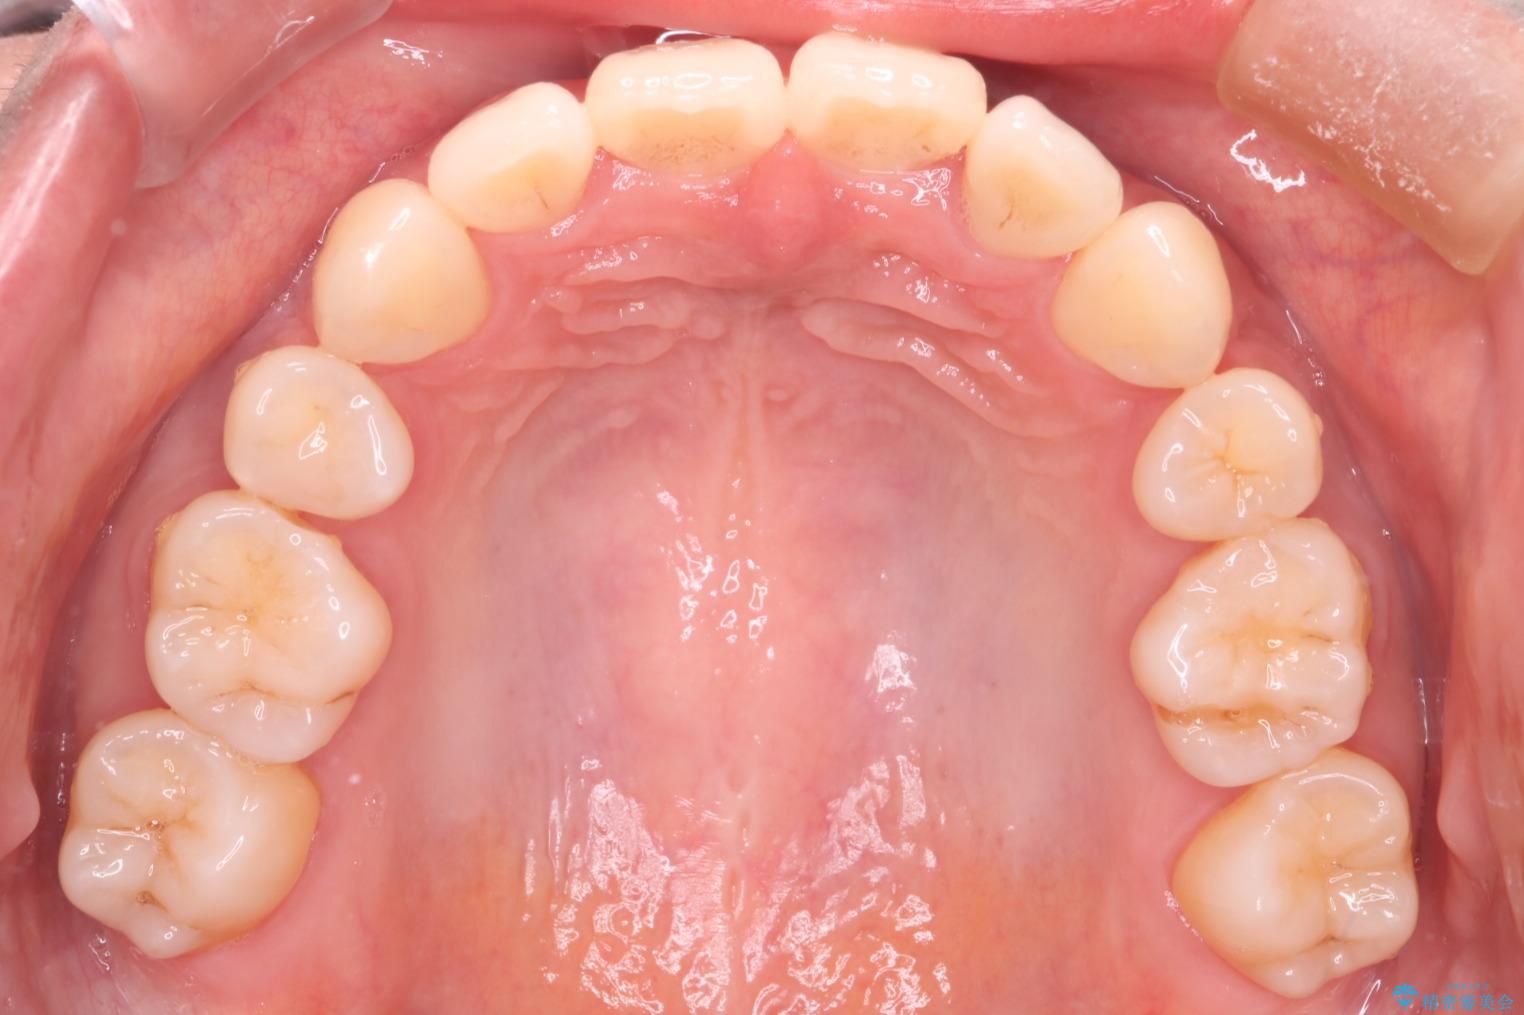

上の前歯のデコボコを主訴にご来院された患者様です。

重度の叢生が認められたため、上下左右4番目の歯を抜歯しワイヤー矯正治療を行いました。

前歯のデコボコが改善され、噛みあわせも綺麗になりました。